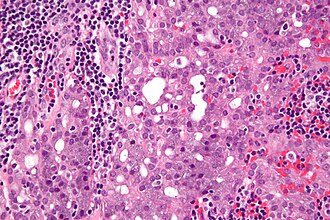

Acinic cell carcinoma. H&E stain. | |

| LM | "acinic cells" (abundant finely vacuolated cytoplasm with basophilic granules, small nuclei with stippled chromatin), scattered "intercalcated duct type cells" (eosinophilic cytoplasm with moderate amount of cytoplasm and bland nuclei), +/-peri-tumoural lymphocytes, +/-glassy extracellular bluish/purple blobs |

- Sheets of acinic cells with:

- Abundant finely vacuolated cytoplasm with basophilic granules - key feature.

- Granules may be focal.

- Small nuclei stippled chromatin.

- Scattered intercalcated duct type cells with:

- Eosinophilic cytoplasm with moderate amount of cytoplasm.

- Bland nuclei with slightly larger than seen in acinic cells.

- +/-Peri-tumoural lymphocytes.

- +/-Glassy extracellular bluish/purple blobs.